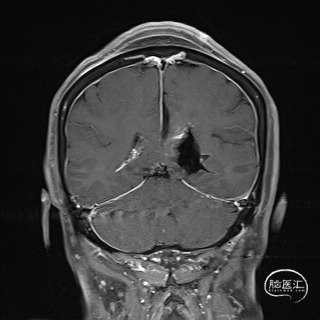

患者 女,66岁,因“头晕5年加重10天”入院。

患者头晕5年加重10天。

外院影像考虑脑膜瘤?室管膜瘤?

诊断:1.颅内占位性病变(左侧侧脑室三角区,脑膜瘤)2.高血压

2023.04.21外院MR

1.结合病史体征及辅助检查诊断左侧侧脑室三角区脑膜瘤明确;

2.肿瘤具有明显的占位效应,无明显的手术禁忌,故手术切除指征明确;